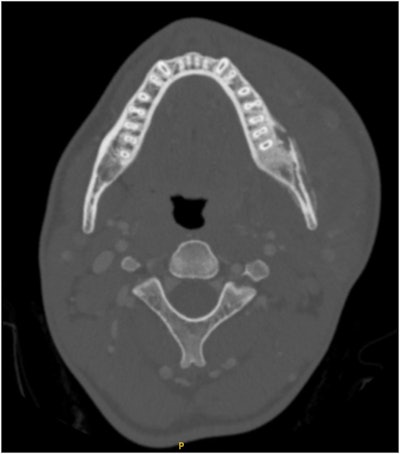

An axial CT scan demonstrates severe left hemimandible osteomyelitis with medullary and cortical osteolytic destruction and sclerosis, with small abscesses on the buccal side of the mandible. There is evidence of left masseter myositis and significant swelling of the masticator and left lingual space.Images courtesy of Podolsky et al. Licensed under CC BY-NC-ND 4.0.

A case report published in February 2025 described a rare instance of Lemierre syndrome in a healthy teen following sepsis from mandibular osteomyelitis after routine third-molar extraction, as revealed by x-ray and computed tomography scans.

The infection led to septic thrombophlebitis of the internal jugular vein, marking what is believed to be the first reported case of its kind in an otherwise healthy adolescent patient. The 17-year-old made a full recovery after prompt surgical debridement, antibiotics, and anticoagulant therapy.